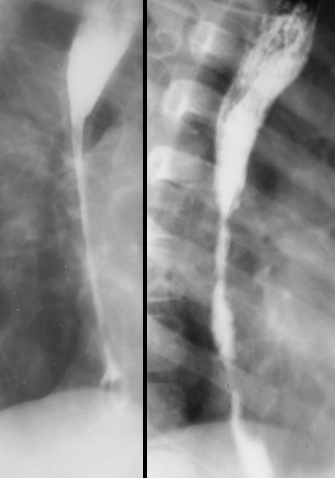

Diverticul Zenker